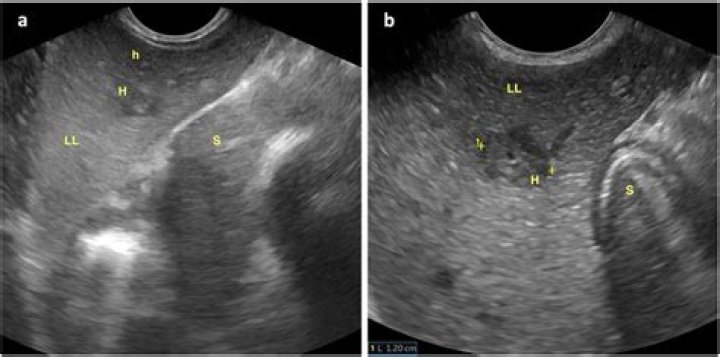

Echo-rich periportal cuffing (ErPC) constitutes a rare ultrasonographic phenomenon characterized by periportal encasement of the liver, also referred to as